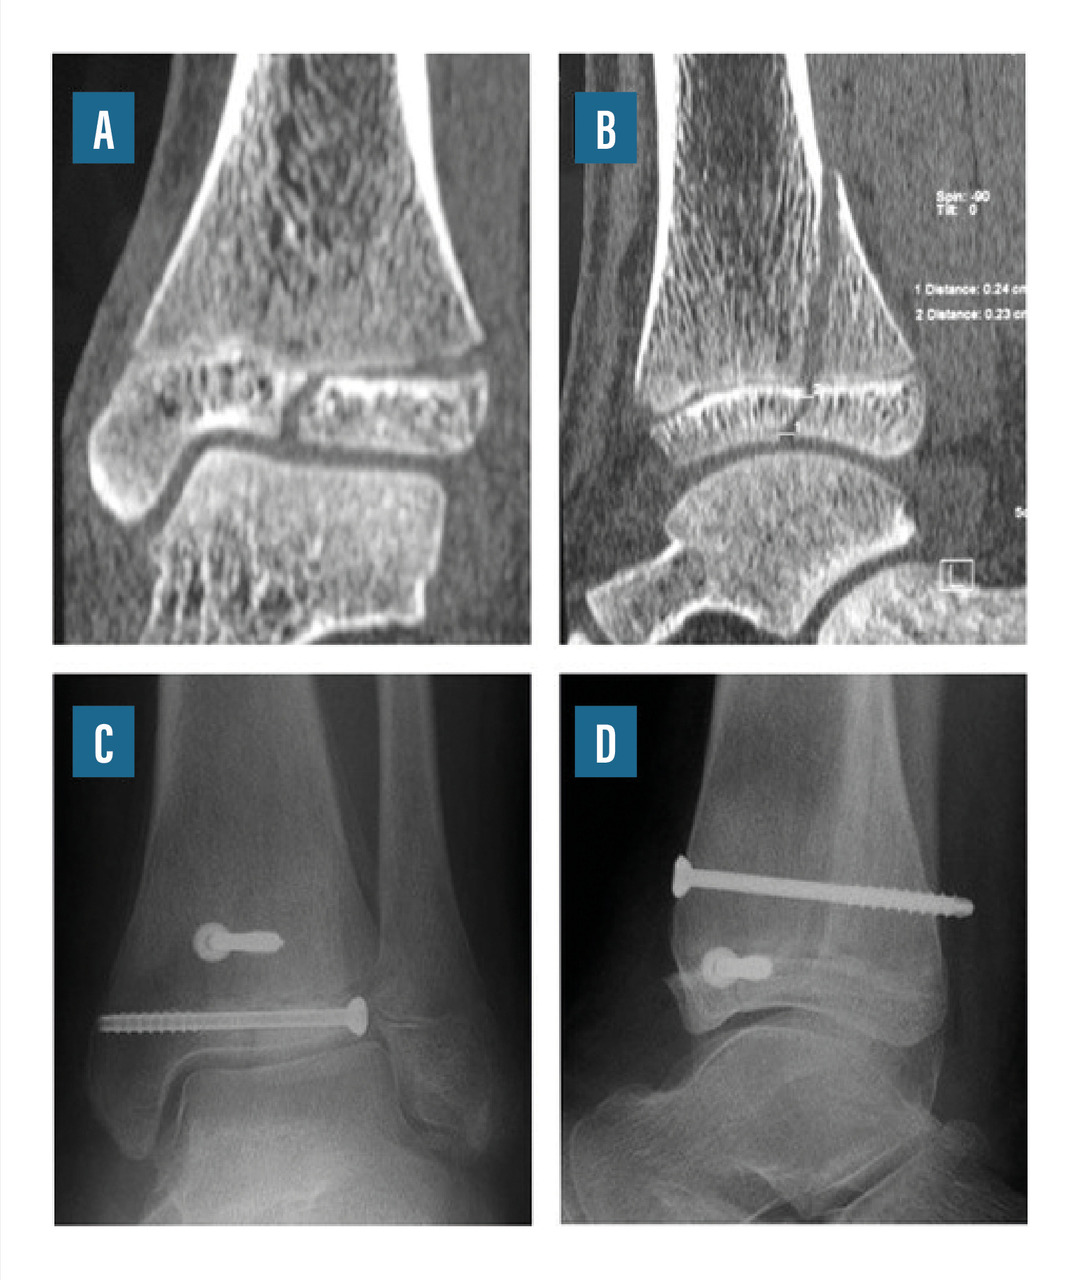

• le vissage percutané par vis canulée montée sur des broches (fig. 9) ;

Les fractures-décollements épiphysaires de type Salter III ou IV posent les problèmes spécifiques du trouble de croissance éventuel et des lésions d’arthrose articulaire à long terme. La fracture de Tillaux représente une forme particulière de fracture de type III : elle survient chez le grand enfant qui a déjà soudé une partie de la zone de croissance. Les fractures déplacées imposent une réduction parfaite, soit en technique percutanée sous contrôle radiologique, soit à foyer ouvert avec contrôle visuel.

La fracture de Mac Farland est une fracture de type Salter III ou IV consécutive à un mouvement d’adduction du pied. Elles peuvent survenir chez des enfants jeunes et ont, dans ce cas, un risque élevé de trouble de croissance et, à terme, de défaut d’axe de la cheville. Les fractures déplacées imposent une réduction parfaite, soit en technique percutanée sous contrôle radiologique, soit à foyer ouvert avec contrôle visuel.